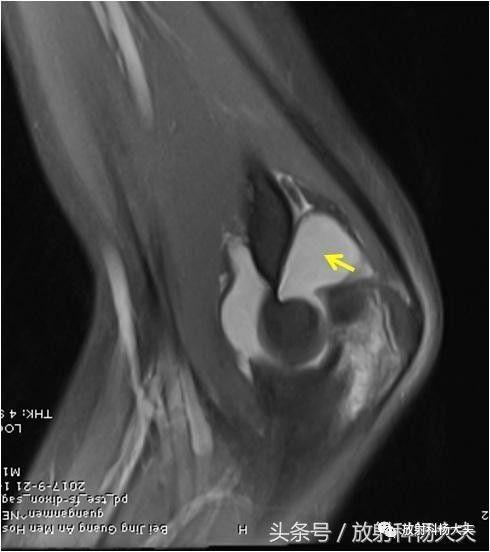

肘侧横突无明显骨折或关节积液. 有二分鹰嘴(箭头).

关节内积液